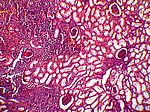

Chron. rezidivierende Pyelonephritis, HE